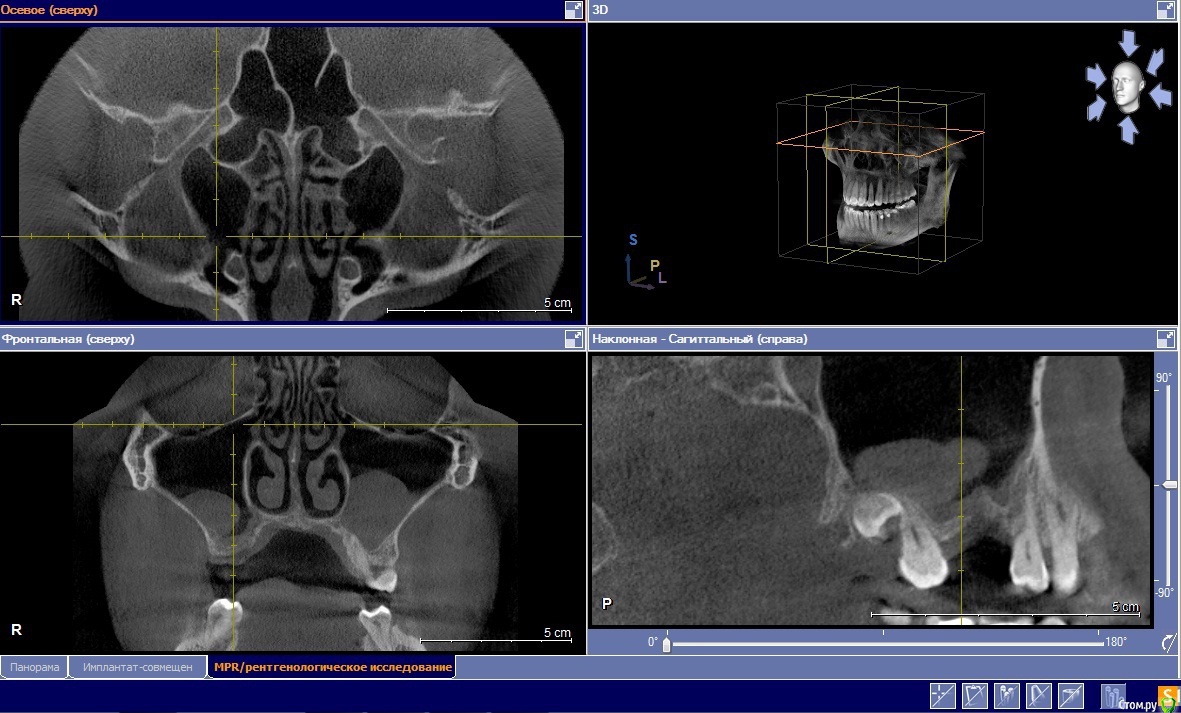

Коллеги выскажите свое мнение о необходимости ЛОР санации верхнечелюстных синусов.

Планируется открытый синус лифтинг+НКР справа.

Больной жалоб кроме как на отсутствие зуба, не предъявляет.

Мое мнение санация необходима.